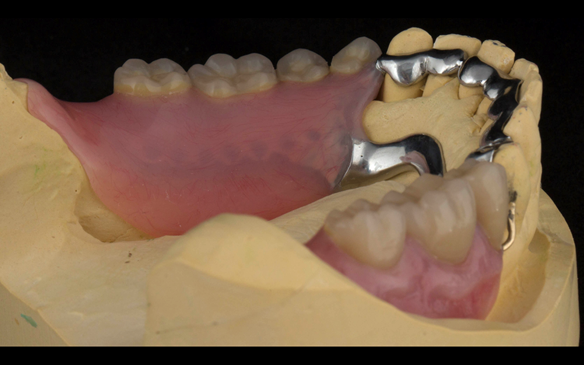

This newsletter describes in step by step detail the transition from acrylic based immediate dentures to metal based definitive dentures.

- Definitive dentures (Mk 2) – complete upper metal reinforced and lower cobalt chromium based partial of hygienic Scandinavian design to be made 9 - 12 months after extractions of all upper teeth and LR5 and LL4